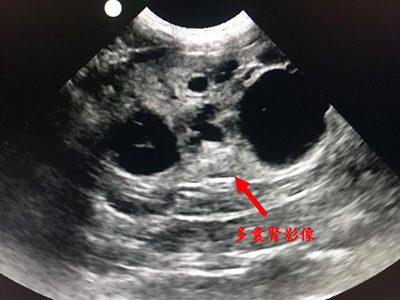

• 貓咪酒精注射腎臟囊腫抽吸 治療多囊腎病

貓咪酒精注射腎臟囊腫抽吸 治療多囊腎病

• 可怕的先天性腎臟病-貓的多囊腎

可怕的先天性腎臟病-貓的多囊腎